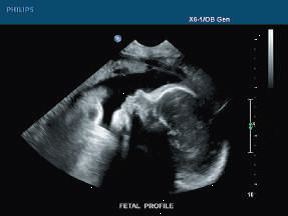

Ultrasonido de diagnóstico. El ultrasonido de diagnóstico es capaz de producir imágenes no invasivas de los órganos internos del cuerpo. Sin embargo, no es bueno para producir imágenes de los huesos o tejidos que contienen aire, como los pulmones. Bajo algunas condiciones, el ultrasonido puede producir imágenes de los huesos (como en un feto o en bebés pequeños) o de los pulmones, cuando están llenos o parcialmente llenos de fluido. Uno de los usos más comunes del ultrasonido es durante el embarazo, para monitorear el crecimiento y el desarrollo del feto, pero tiene muchos otros usos, incluyendo producir imágenes del corazón, vasos sanguíneos, ojos, tiroides, cerebro, tórax, órganos abdominales, piel y músculos. Las imágenes de ultrasonido se despliegan en 2D, 3D o 4D (lo que es 3D en movimiento).